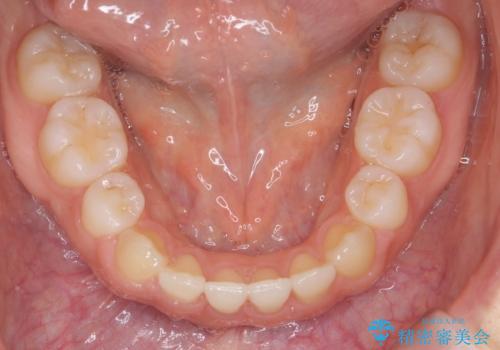

時間はかかりましたがしっかりかみ合わせから治すことができました。

口元の突出も改善しており理想的な横顔になりました。